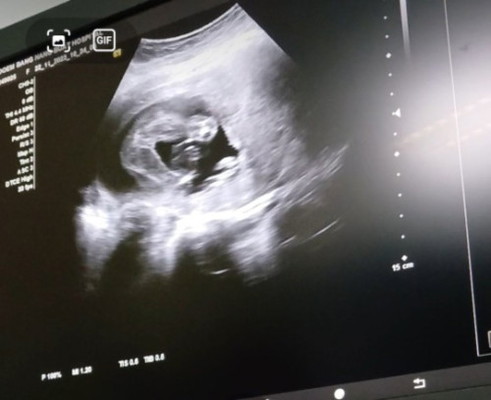

แม่ๆมองเพศน้องออกมั้ยคะ

อยากรู้เพศลูกค่ะ แม่ๆมองออกมั้ยคะ

ลูกสาวไหมคะ แอบคล้ายของแม่บ้านนี้อยู่นะคะ😅

เหมือนกันไหมคะบ้านนี้หมอบอกว่าลูกสาวค่ะ

ผญ ไหมค่ะ เหมือนน้องจะมีกลีบๆ อิอิ

น่าจะเป็นลูกสาว นะคะ ☺️

ลูกสาวคะแม่

หญิงค่ะแม่😍😍